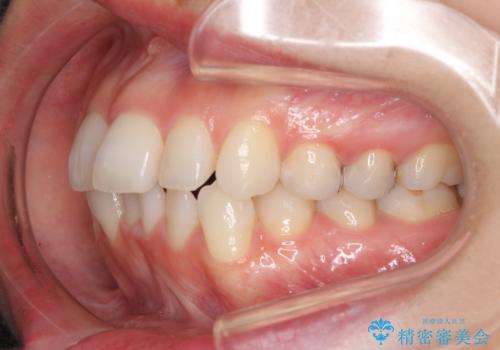

【モニター】前歯のデコボコをインビザラインできれいに整える

- 前歯のデコボコを気にして来院された患者様です。

主に下顎歯列全体の後方移動とIPR(歯と歯の間を削る)によってデコボコが解消するように設計し、インビザラインにより治療を行うこととしました。

舌突出癖がある方ですと、叢生が解消すると同時に前方に拡大されてしまいますが、ゴムかけをしっかりと行ってくださったこともあり、スッキリとした仕上がりとなりました。